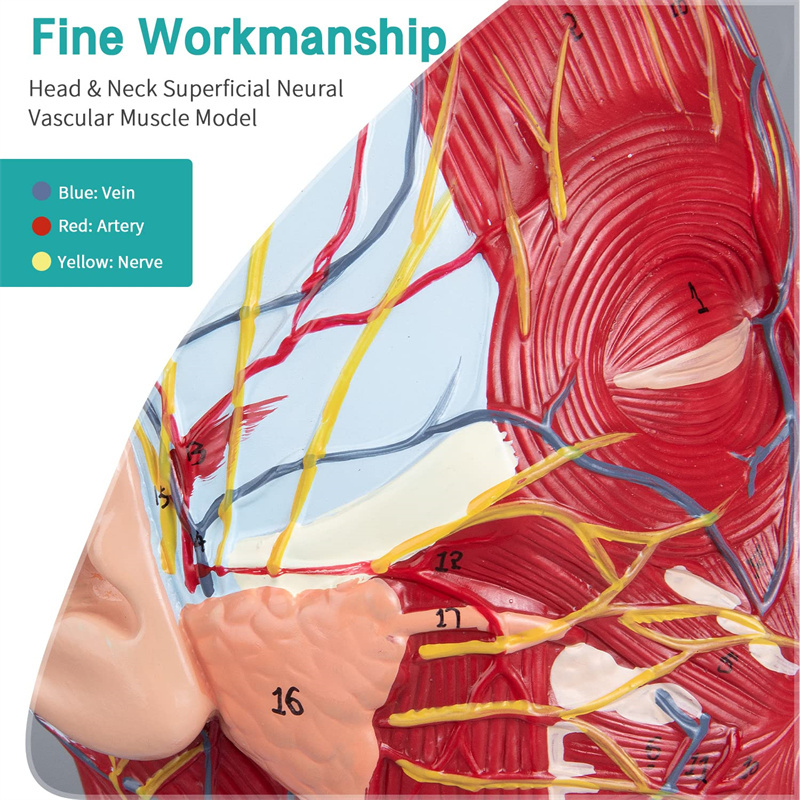

【Mudell tal-muskolu newrovaskulari superfiċjali】 Dettaljat ħafna, numri mmarkati, li jistgħu jinqalgħu, japprofondixxu l-fehim tal-muskoli superfiċjali, bastimenti, nervituri u l-istrutturi interni tar-ras u l-għonq. Arterja ħamra, vetta blu, isfar-nerve.

【Karatteristiċi】 Juri l-muskoli superfiċjali tal-wiċċ espost; il-bastimenti tad-demm superfiċjali u n-nervituri tal-wiċċ u l-qorriegħa; l-istrutturi ta 'ġewwa tal-glandola parotida u l-passaġġ respiratorju ta' fuq; L-istruttura tas-sezzjoni trasversali sagittali tas-sinsla ċervikali.

Dan il-mudell juri dettalji tal-għonq tar-ras tal-lemin u s-sezzjoni sagittali tan-nofs tal-bniedem. inkluż is-superfiċjali

muskoli tal-wiċċ espost; il-bastimenti tad-demm superfiċjali u n-nervituri tal-wiċċ u l-qorriegħa; l-istrutturi ta 'ġewwa

tal-glandola parotida u l-passaġġ respiratorju ta 'fuq; L-istruttura tas-sezzjoni trasversali sagittali tas-sinsla ċervikali.

Dan il-mudell huwa mudell ta 'muskolu newrovaskulari superfiċjali ta' ras u għonq naturali, komponent 1, li juri d-dettalji tar-ras tal-lemin u l-għonq u s-sezzjoni sagittali medjana, inklużi l-muskoli superfiċjali esposti tal-wiċċ, bastimenti superfiċjali tal-wiċċ u l-qorriegħa, in-nervituri u l-istruttura medjali tal-glandola parotida u l-passaġġ respiratorju ta 'fuq, u l-istruttura tas-sezzjoni sagittali tas-sinsla ċervikali